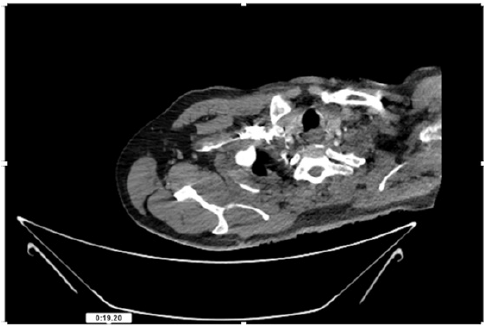

55-years-old chronic smoker had acute, severe pain in the right upper limb for one week; it was cold upto mid arm with skin discoloration. He also noticed numbness and weakness of movement of elbow joint. He underwent below elbow amputation in February 2023 for acute ischemia of left upper limb. He was a current chronic smoker; 15 pack year. General condition was weak; temperature was normal; blood pressure was 100/60mmHg; heart rate was 92/minutes with sinus rhythm; SpO2 was 97% on air; heart was normal. In lower extremities, all peripheral pulses were intact. Local Examination of right upper limb revealed as follows: tenderness; coldness; discoloration; decreased motor function and sensory modalities. Axillary, brachial and radial pulses were not palpable. Hand-held Doppler failed to detect any signal in arterial system; therefore, we arranged for emergency embolectomy. complete occlusion of right upper limb arterial system Full blood count showed high hemoglobin (14.6gm%); normal total WBC and platelet count. Coagulation profile was normal. Parenteral unfractionated heparin, antibiotics, tramadol, proton-pump inhibitors, anti-platelets and HMG CoA reductase inhibitors were given. Doppler ultrasound demonstrated complete occlusion of right upper limb arterial system. CT Angiogram illustrated occlusion of subclavian artery downwards on both sides. Figures 1-14 shows complete occlusion of right subclavian artery without collaterals. On Day ‘2’ of admission, the patient passed black tarry stool for 3 times. However, the vital signs were stable; blood pressure was 100/60mmHg; heart rate was 92/min; SpO2 was 97% on air; the abdomen was soft and not tender. Above elbow amputation was done on Day ‘2’ of admission. Intra-operative findings were as follows: (1) no active bleeding at brachial artery; (2) thrombosis along brachial artery; (3) muscle color and consistency were not healthy.

Figure 4: CT Angiogram at neck showing normal brachio-cephalic trunk, common carotid artery, and narrow right subclavian artery.

Figure 5: CT Angiogram at neck showing normal brachio-cephalic trunk, common carotid artery, and narrow right subclavian artery.

Figure 6: CT Angiogram at neck showing brachio-cephalic trunk, common carotid artery and narrow right subclavian artery.

Figure 7: CT Angiogram at neck showing brachio-cephalic trunk, common carotid artery and narrow right subclavian artery.